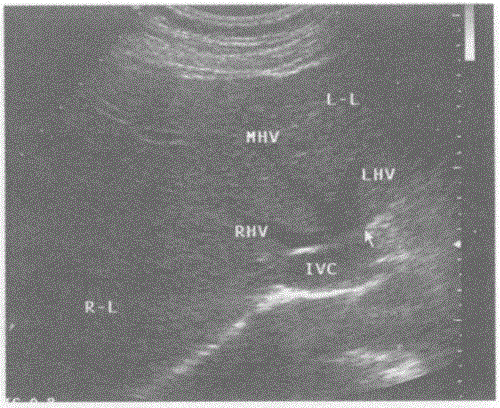

问题 下图是肝脏横切正常超声图像,请回答箭头所指部位的解剖名称:

选项 A.门静脉主干 B.第一肝门 C.第二肝门 D.肝静脉

答案 C